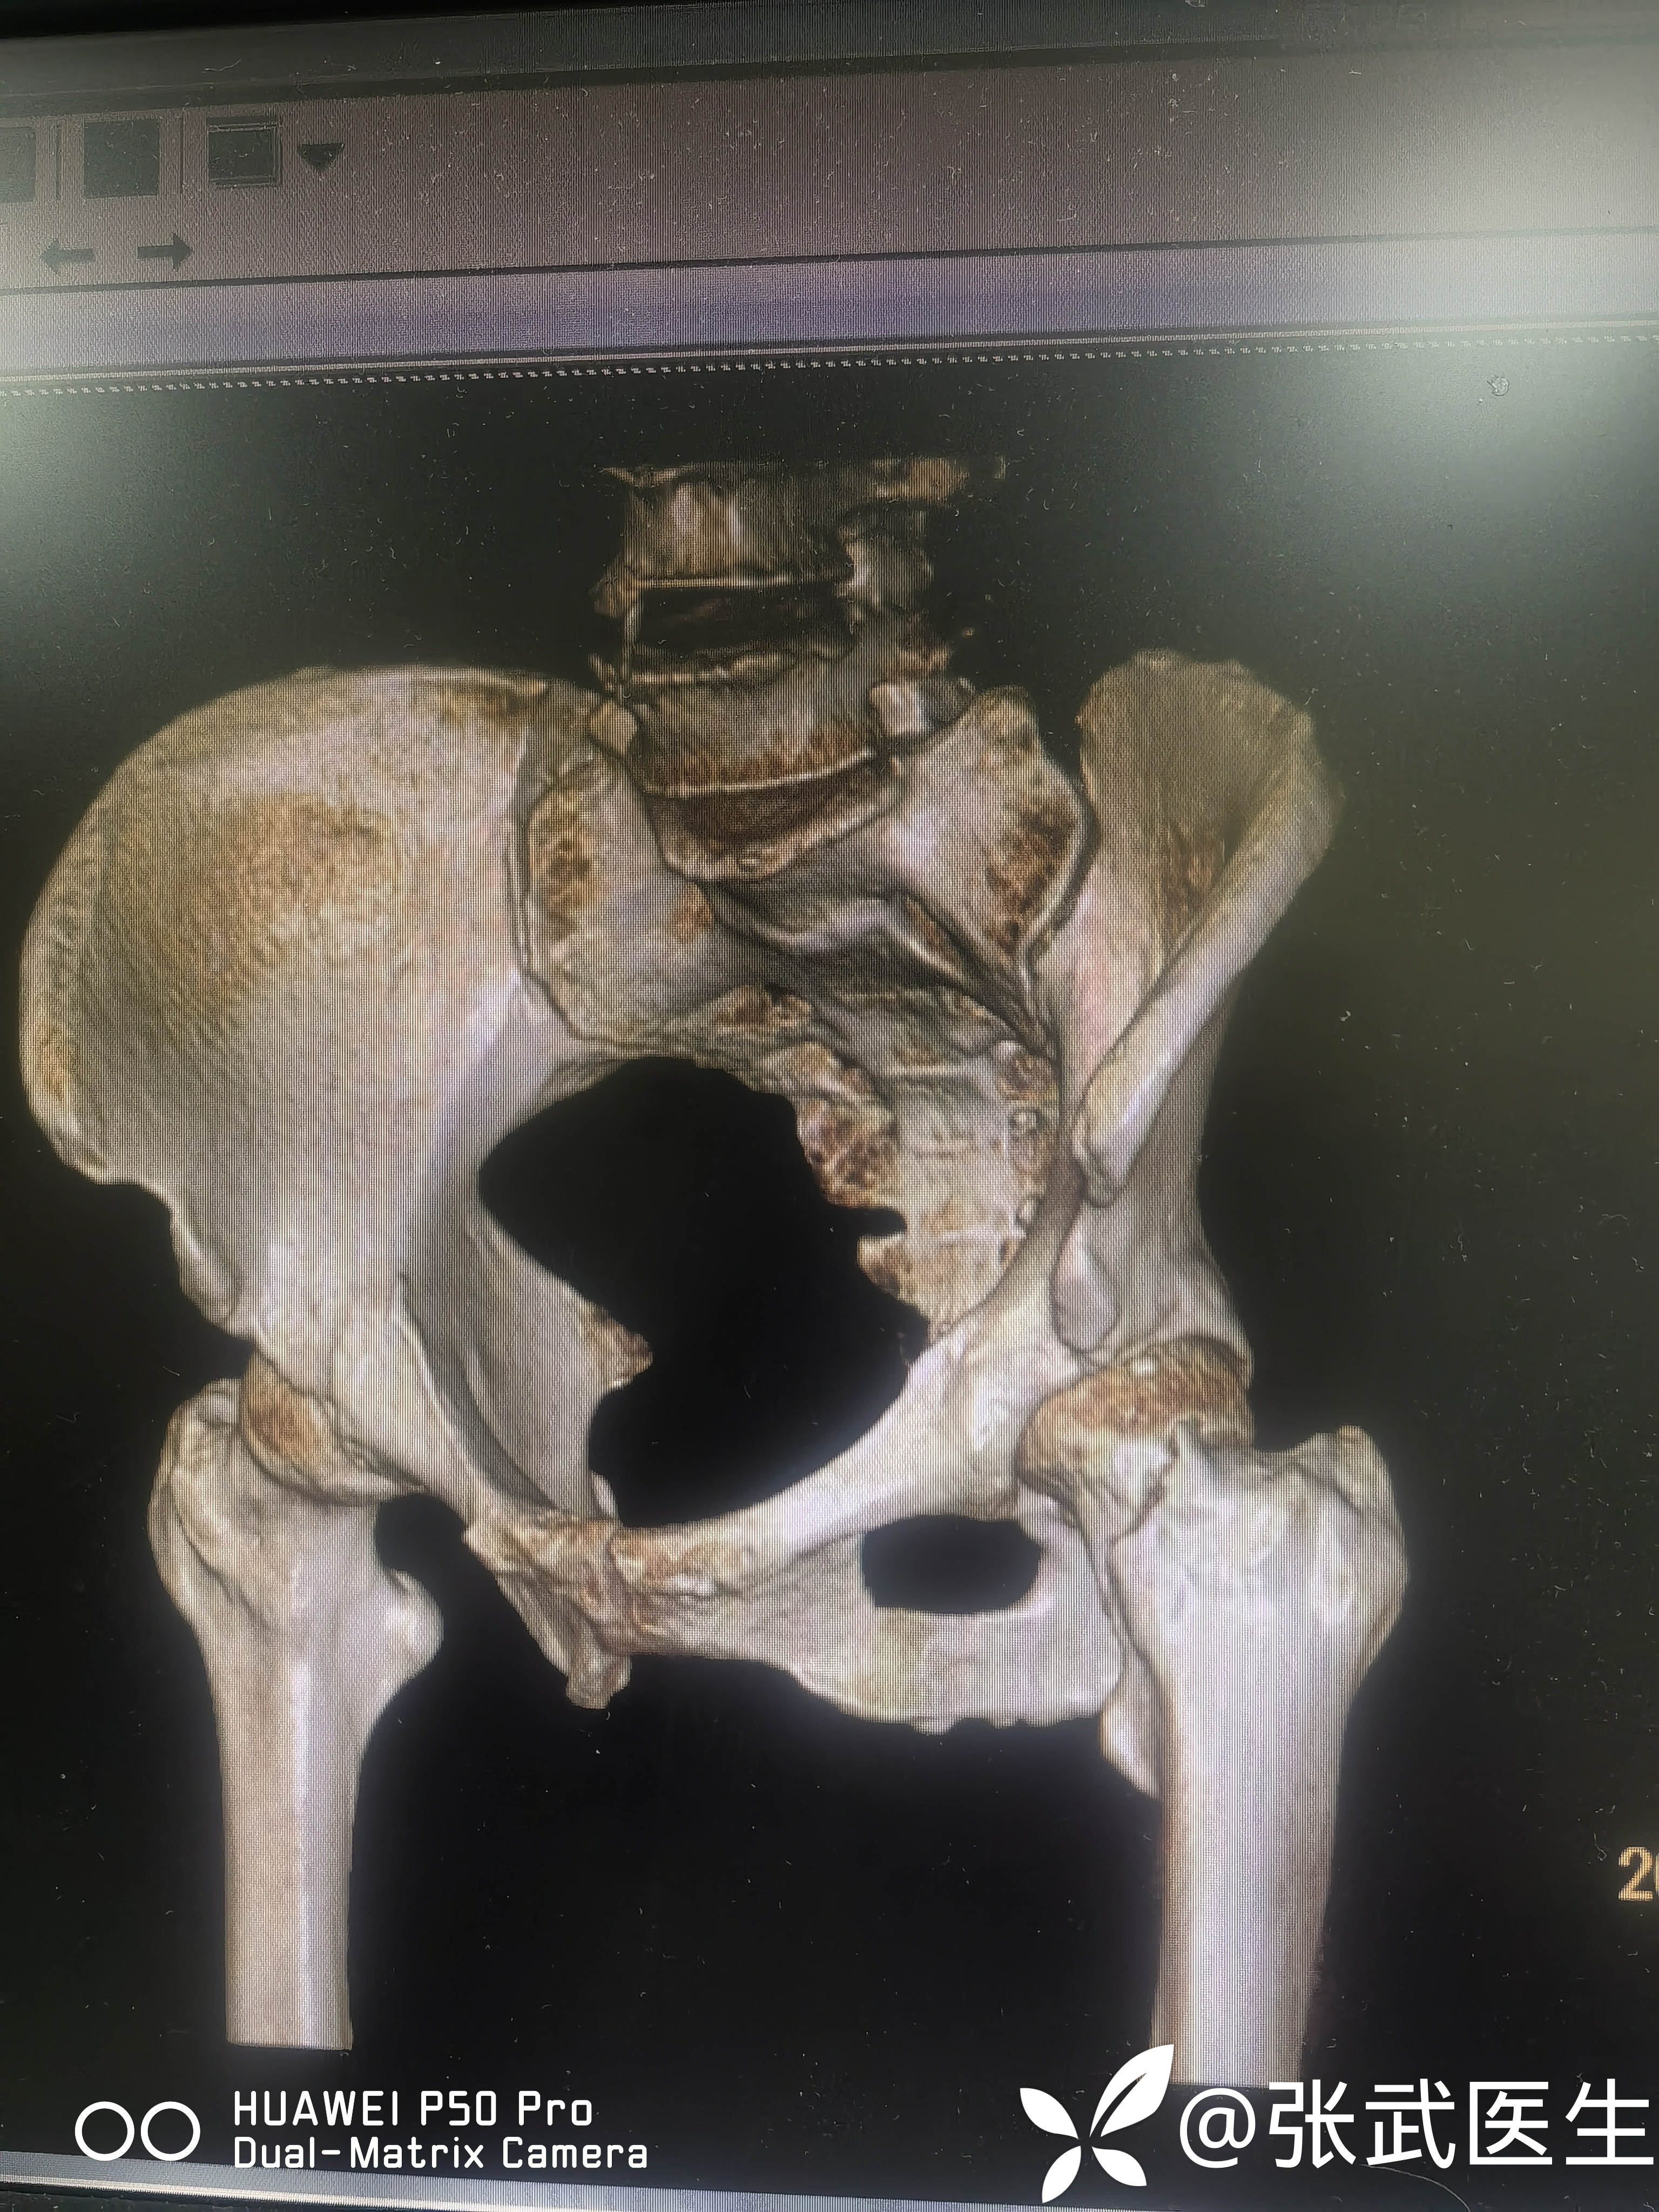

诊断:左股骨颈骨折 Garden II型

术前:

pauwels>50度